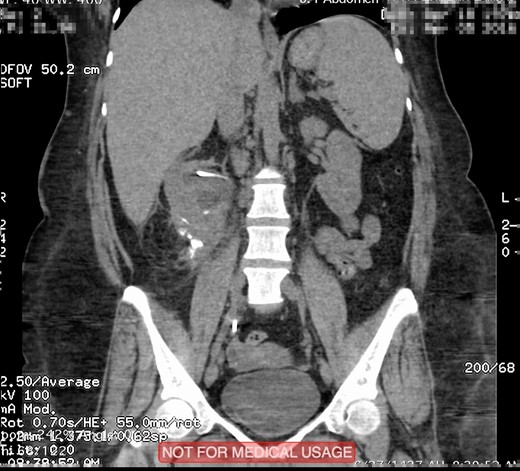

This is a 45-year-old female patient known to have diabetes mellitus and old cerebrovascular attack presented with right flank pain. Laboratory investigations revealed normal WBC count with a hemoglobin 10.4 mg/l. Radiological investigation showed right a 20 mm right renal stone (Fig. 1). Patient underwent FURS-L using a 10/12Fr Ureteral Access sheath. We did endoscopic renal exploration plus laser lithotripsy using Flex-Xc STORZ. The irrigation was under hydrostatic pressure of 80 cm H2O. The procedure was uneventful with an operative duration of 88 minutes. However, severe extravasation was noted at the end (Fig. 2). Six hours postoperatively the patient started to have high grade fever with a sudden drop of hemoglobin level to 6.6 mg/l. Immediate abdominopelvic CT scan with contrast was carried out showing severe right subcapsular renal hematoma. This complication was managed conservatively through proper antibiotics, blood transfusion and good hydration for 7 days. The patient was seen in the outpatient clinic 2 months later with a new abdominopelvic CT scan which showed a regression of subcapsular renal hematoma and surprisingly migration of stone fragments into the regressed subcapsular hematoma (Fig. 3). On the other hand, the upper urinary tract was free of stones.

Plain abdominopelvic CT, coronal view showed migrated stone fragments into the regressed right subcapsular renal hematoma.

Subcapsular renal hematoma (SRH) is an uncommon complication and it is rarely described after FURS-L. The first detailed case was reported by Bansal et al. [1] Bai and colleagues summarized 2848 patients post FURS-L, SRH was reported in 11 patients (0.4%) [2]. Out of 11 patients three resolved completely without intervention, six were managed with a percutaneous drainage, while two underwent open surgery with lumber incision. Chiu and colleagues reported a similar incidence of SRH post FURS-L [3]. In the series, they reported 4 (0.36%) SRH after 1114 FURS-L. Risk factors of SRH mentioned by Bai and co-workers include larger stone size (1.4 vs 0.9 cm), severe ipsilateral hydronephrosis, longer operation duration (41 vs 33 min), and higher perfusion pressure of hydraulic irrigation (176.8 vs 170.2 mm Hg) [2]. We presented our case out of 250 patients underwent FURS-L, this represented 0.4%, which is comparable to previous studies [1–3]. In our case, conservative management was sufficient. However, as mentioned by Chiu and colleagues the management of SRH should be customized for each patient. As far as we know, our case report is the first complication in the world where stone fragments migrated into perinephric space. Although we had no obvious trauma to pelvicalyceal system and the operative procedure was uneventful the most probable etiology of this incidence is due to forniceal rupture caused by high pressure or guidewire manipulation aggravated by longer operative time as mentioned by Bansal and colleagues [1].